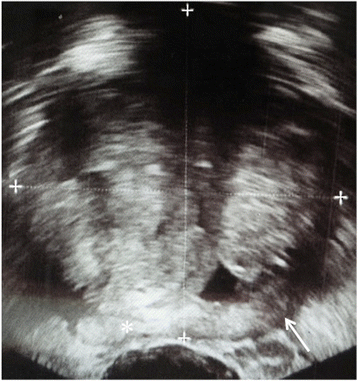

Multi-parametric prostate MR imaging revealed no abnormality in the central, transitional or peripheral zones of the prostate gland. However, in the left seminal vesicle and non-contiguous with the adjacent prostate gland or capsule, there was an abnormal 1.5 × 1.2 × 1.0 cm lesion with conspicuous hypointense T2-weighted (T2W) signal intensity seen on high-resolution axial imaging (Fig. 1a). High-resolution coronal and sagittal T2W images show, to advantage, this lesion within the left seminal vesicle (Fig. 1b-c), external to the prostate gland capsule, which is maintained with normal signal intensity and morphology. No T2W signal intensity abnormality is seen in the adjacent left prostate gland base related to the left seminal vesicular abnormality. Moreover, there is no exophytic hyperplastic nodule or contiguous extension of prostatic glandular tissue related to the abnormality in the left seminal vesicle. On high b-value diffusion weighted imaging (DWI) and apparent diffusion coefficient (ADC) map, this lesion features significantly diminished diffusivity with low ADC mean value of 0.5 × 10−3 mm2/s (Fig. 1d-e). There is no abnormal diffusivity in the adjacent or regional left prostate gland base peripheral or transitional zone related to the left seminal vesicular abnormality. Pre- and post-contrast fat-saturated T1-weighted (T1W) imaging obtained prior to and following the infusion of intravenous gadolinium contrast show abnormal perfusion of this lesion (Fig. 2a-b). Abnormal perfusion pattern of this lesion is confirmed with CAD, which demonstrates early enhancement with partial washout and colorimetric stratification of ‘green’ and ‘red’: indeterminate/suspicious (‘green’) and highly suspicious (‘red’) (Fig. 2c dashed arrow and solid arrow). The hyperperfused lesion in the left central zone with highly suspicious enhancement (Fig. 2c asterisk) demonstrated relative hypointensity on T2W imaging with thin, circumscribed hypointense periphery, and no diminished diffusivity, compatible with a hyperplastic (BPH) stromal nodule that was later confirmed on MR imaging-TRUS fusion biopsy with no malignancy on tissue histopathological sampling. This lesion was reported as clinically significant cancer is highly likely to be present; it was subsequently targeted on MR imaging-TRUS software-based fusion biopsy. Repeat 14-core TRUS biopsy, supplemented with targeted MR imaging-ultrasound fusion-guidance, was performed of the prostate gland and left seminal vesicle. Ultrasound gray-scale imaging from the fusion biopsy confirms an abnormal hypoechoic lesion in the left seminal vesicle (Fig. 3).